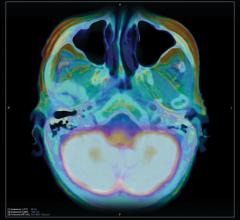

Advanced imaging and hybrid modalities, such as computed tomography (CT), magnetic resonance imaging (MRI), positron emission tomography (PET)/CT and single-photon emission computed tomography (SPECT)/CT are showing significant growth and will continue to do so, despite some slowdown in overall imaging volume due to the changing reimbursement landscape.